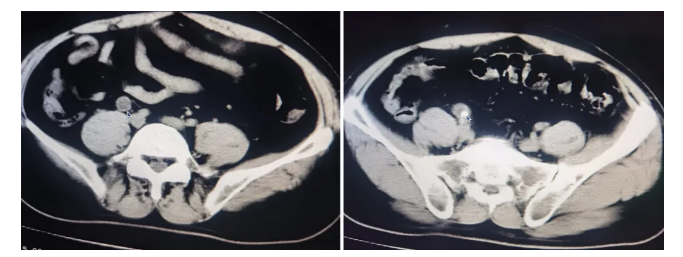

通过对患者蔡先生看诊,并结合腹部CT拍片、体格检查和相关辅助检查后,周先发医师诊断为“右侧输尿管结石并重度积水;双肾结石”。

腹部CT拍片